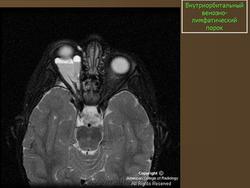

Лимфангиома орбиты (син.: сосудистая гамартома, венолимфатическая мальформация)

Врожденная доброкачественная сосудистая опухоль, которая состоит из расширенных сосудов, окруженных лимфатической тканью.

В большинстве случаев ограничивается конъюнктивой. Лимфангиомы орбиты прогрессивно увеличиваются в размерах, не склонны к спонтанной инволюции. В отличие от капиллярных гемангиом, которые часто подвергаются обратному развитию. Составляют менее 5% опухолей глазницы у детей. Могут сочетаться с лимфангиомами других локализаций. В норме в глазнице лимфатическая ткань не определяется.

Наиболее типичная черта: выявление уровней жидкости в образовании, за счет спонтанных кровотечений.

Экстраорбитальное (но может быть рапсоалагаться как в канале, так вне его), мультикистозное, мультифокальное объемное образование с неправильным контуром.

Гиперденсное, по плотности сопоставимо с мышечной тканью, негомогенной структуры образование, пересекает анатомические границы. Стенка лимфангиомы вариабельно накапливает КВ. Тип краевого накопления КВ иногда позволяет установить умеренное ремоделирование прилежащей кости. В структуре образования иногда определяются небольшие кальцинаты или флеболиты.